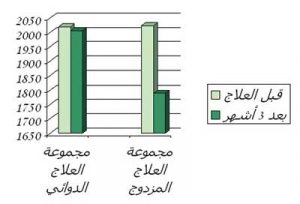

يوضح الرسم تأثير العلاج المزدوج والعلاج الدوائي منفردا على مؤشرات نشاط المرض اللإكلينيكية في كل مجموعة

يوضح الرسم تأثير العلاج المزدوج والعلاج الدوائي منفردا على مؤشرات نشاط المرض اللإكلينيكية في كل مجموعة

أظهر العلاج المزدوج تفوقا ملحوظا على العلاج الدوائي بمفرده , وأوضحت الدراسة وجود فارق ذا دلالة إحصائية بين مجموعة العلاج المزدوج ومجموعة العلاج الدوائي شمل جميع المؤشرات الإكلينيكية و المعملية لنشاط المرض, وقد أسفر البحث عن النتائج التالية:

أولاً: نتائج الفحص الإكلينيكي (السريري) لدلالات نشاط الروماتويد:

• بعد ثلاثة أشهر من العلاج:

انخفضت بشكل ملحوظ مؤشرات (دلالات) نشاط المرض اللإكلينيكية في كل من المجموعتين ولكن كان الانخفاض سريعا في مجموعة العلاج المزدوج (بعد الشهر الأول من اضافة الحجامة إلى العلاج الدوائي) بينما كان الانخفاض متأخرا في مجموعة العلاج الدوائي (بعد الشهر الثالث من العلاج الدوائي منفردا).